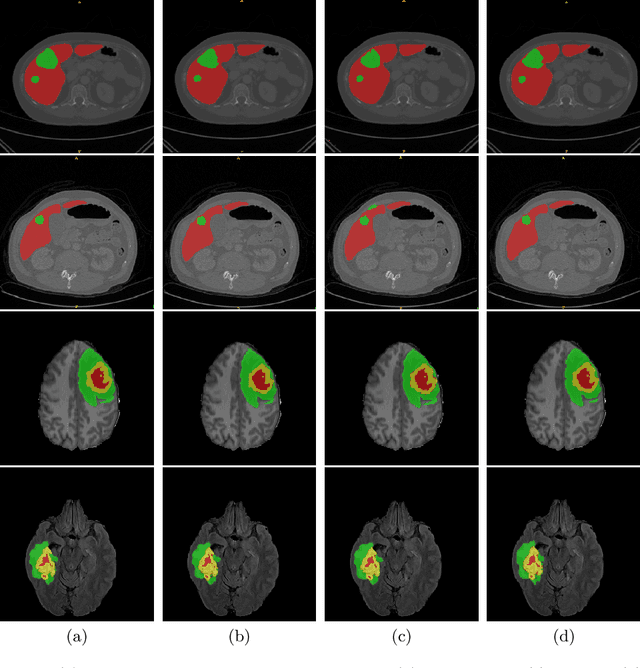

Abstract:Vision Transformers (ViT)s have recently become popular due to their outstanding modeling capabilities, in particular for capturing long-range information, and scalability to dataset and model sizes which has led to state-of-the-art performance in various computer vision and medical image analysis tasks. In this work, we introduce a unified framework consisting of two architectures, dubbed UNetFormer, with a 3D Swin Transformer-based encoder and Convolutional Neural Network (CNN) and transformer-based decoders. In the proposed model, the encoder is linked to the decoder via skip connections at five different resolutions with deep supervision. The design of proposed architecture allows for meeting a wide range of trade-off requirements between accuracy and computational cost. In addition, we present a methodology for self-supervised pre-training of the encoder backbone via learning to predict randomly masked volumetric tokens using contextual information of visible tokens. We pre-train our framework on a cohort of $5050$ CT images, gathered from publicly available CT datasets, and present a systematic investigation of various components such as masking ratio and patch size that affect the representation learning capability and performance of downstream tasks. We validate the effectiveness of our pre-training approach by fine-tuning and testing our model on liver and liver tumor segmentation task using the Medical Segmentation Decathlon (MSD) dataset and achieve state-of-the-art performance in terms of various segmentation metrics. To demonstrate its generalizability, we train and test the model on BraTS 21 dataset for brain tumor segmentation using MRI images and outperform other methods in terms of Dice score. Code: https://github.com/Project-MONAI/research-contributions

Abstract:Semantic segmentation of brain tumors is a fundamental medical image analysis task involving multiple MRI imaging modalities that can assist clinicians in diagnosing the patient and successively studying the progression of the malignant entity. In recent years, Fully Convolutional Neural Networks (FCNNs) approaches have become the de facto standard for 3D medical image segmentation. The popular "U-shaped" network architecture has achieved state-of-the-art performance benchmarks on different 2D and 3D semantic segmentation tasks and across various imaging modalities. However, due to the limited kernel size of convolution layers in FCNNs, their performance of modeling long-range information is sub-optimal, and this can lead to deficiencies in the segmentation of tumors with variable sizes. On the other hand, transformer models have demonstrated excellent capabilities in capturing such long-range information in multiple domains, including natural language processing and computer vision. Inspired by the success of vision transformers and their variants, we propose a novel segmentation model termed Swin UNEt TRansformers (Swin UNETR). Specifically, the task of 3D brain tumor semantic segmentation is reformulated as a sequence to sequence prediction problem wherein multi-modal input data is projected into a 1D sequence of embedding and used as an input to a hierarchical Swin transformer as the encoder. The swin transformer encoder extracts features at five different resolutions by utilizing shifted windows for computing self-attention and is connected to an FCNN-based decoder at each resolution via skip connections. We have participated in BraTS 2021 segmentation challenge, and our proposed model ranks among the top-performing approaches in the validation phase. Code: https://monai.io/research/swin-unetr